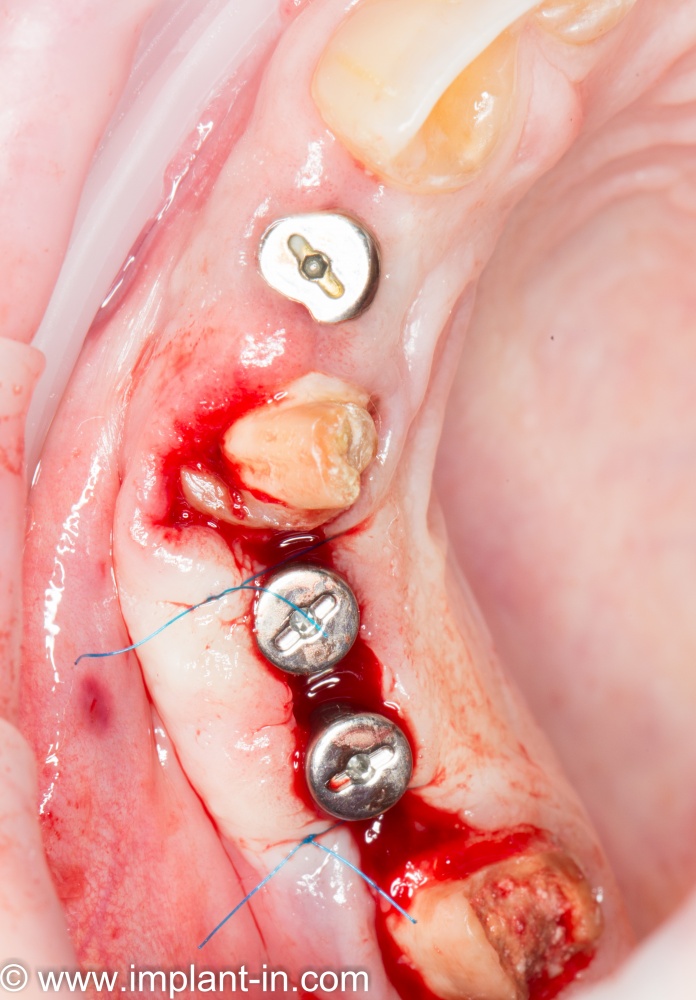

Трансплантация десны, аугментация лунки

Для определения размеров будущего мягкотканного аутотрансплантата мы использовали пародонтологический зонд. С помощью него мы выбрали донорскую зону (бугор верхней челюсти или небная сторона альвеолярного отростка верхней челюсти в области моляров), с помощью скальпеля получили необходимый по размеру аутотрансплантат (мягкотканный лоскут для пересадки).

Затем, мы подготовили ксенографт Bio-Oss Collagen. Обычно на 2 зуба (центральных резца) с избытком хватает 100-миллиграмовой упаковки. Имеющийся в ней параллелепипед мы поделили на 2 усеченные пирамиды с основанием в 2/3 ширины изначального блока.

Если вы когда-нибудь видели подобные операции, то наверняка обращали внимание на порядок действий — сначала устанавливаются имплантаты, затем укладывается графт и только потом фиксируется мягкотканный аутотрансплантат. Для удобства в этом и похожих клинических ситуациях мы поменяли порядок действий:

Сначала мы провели и зафиксировали деэпителизированный соединительнотканный аутотрансплантат (ССТ). Для этого мы сформировали тоннель и использовали ортодонтическую проволоку в качестве проводника. Подробнее об этой методике можно почитать здесь>>.

Затем уложили ксенографт. Особенностями Bio-Oss Collagen являются удобство адаптации, устойчивость к вымыванию и выдавливанию, поэтому мы просто уложили полученные ранее пирамидки вестибулярно относительно будущего имплантата, после чего прижали их с помощью уже упоминавшихся аналогов имплантата, входящих в хирургический набор имплантационной системы Xive (кстати, при работе с другими имплантационными системами для паковки графта в лунке можно использовать круглые остеотомы для синуслифтинга).

В совокупности, аугментация лунок перед установкой имплантатов занимает около 20 минут — и это самый долгий из всех хирургических этапов лечения.